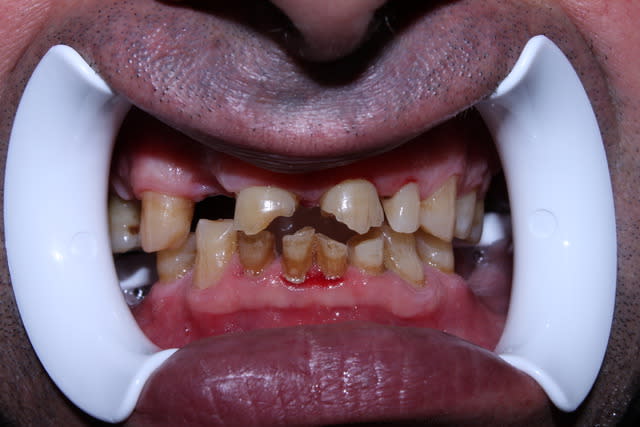

Patient de 70 printemps, en pleine forme, encore actif, aucun traitement médical.

Il vient pour des sensibilités au froid, et envisage une réhabilitation globale.

-hygiène correcte

-Masseters puissants

-ATM fatigue

-les dents sont totalement ancrées dans l'os (pas une ne bouge)

-faces masticatoires bien usées, (sans doute perte de DVO)

-présence de multiples mylolyses du collet

Pour le moment je vous poste l'OPT. Si ce cas vous interesse j'essaierai de poster régulièrement l'évolution.

Sur dents vivantes? ça ne m'enchante guère car on voit très bien par transparence la dentine réactionnaire, la pulpe n'est pas loin.

Pas d'IC me semble compliqué dans le cas présent: quand on voit la pano, on se dit qu'il ne doit pas y avoir gd chose qui dépasse des gencives.

Il faut quand même un minimum de rétention pour pouvoir se contenter de tailler sur dents vivantes; sur les incisives, je ne vois pas comment s'accrocher sans mettre de tenon: c'est plat, la dentine doit être hyper-minéralisée ce qui ne facilite pas le collage... et la hauteur de couronne clinique ne doit pas dépasser 2mm.